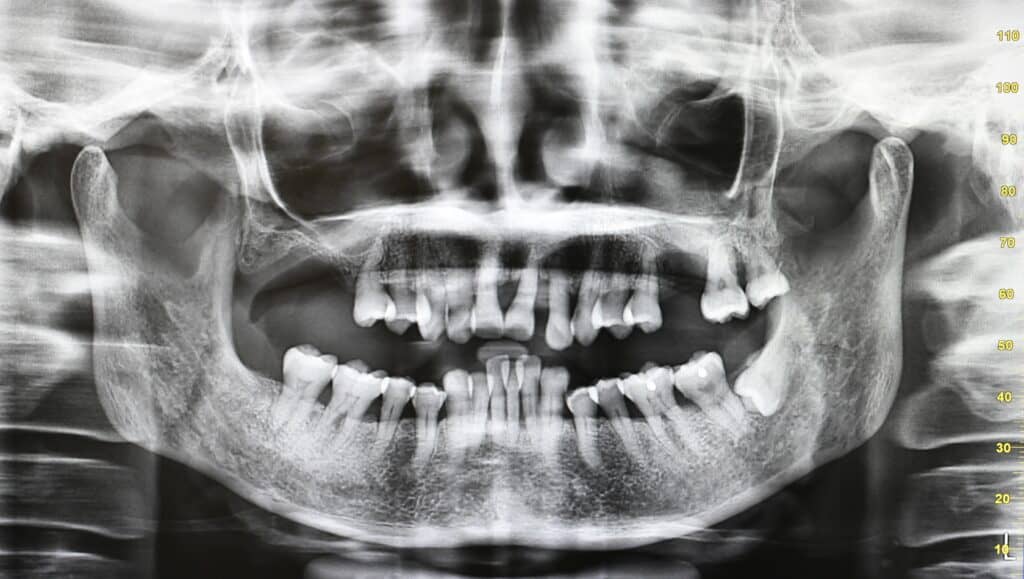

- 牙周袋過深:牙周袋是牙齒與牙肉之間的空隙。當患者口腔內約20%的牙齒出現5毫米或以上的牙周袋,便屬於嚴重牙周病;牙周組織嚴重萎縮,牙齒看似愈來愈長,僅剩三分之一依附牙齦,牙齒的脫落風險極高。

經評估和檢查後,發現原來她的牙周病已達嚴重階段。馮醫生指,必須先採用非侵入性治療,進行深層洗牙,清除大量牙石,最終因有10多顆牙齒已見「郁動」而要脫牙。「盡可能保留病人的所有牙齒,但若病情已無法逆轉,則只有脫牙。」病人由治療至今已逾10多年,一直有定期覆診,並佩戴假牙,配合正確刷牙方法,得以保護其他牙齒的健康。「看到病人最大的改變就是能夠重新投入社交生活,重見笑容。」另外,她的血糖水平也較以前穩定。